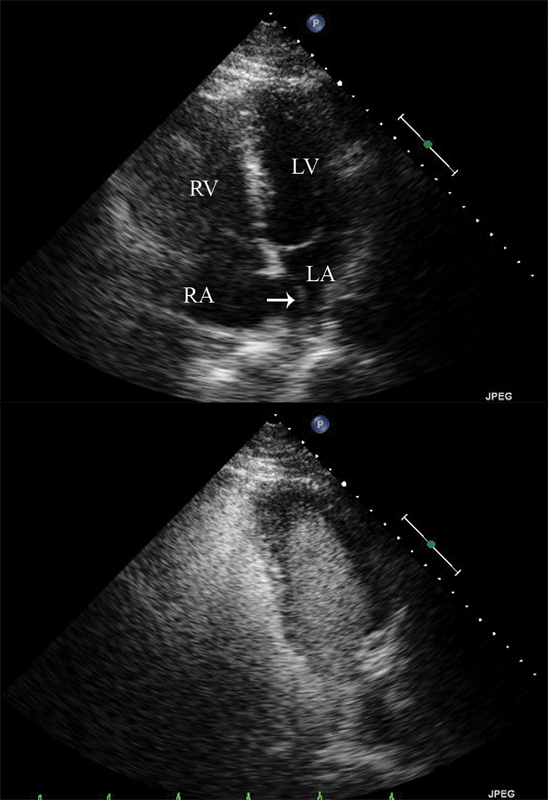

فحوصات تشخيصية لبعض امراض القلب والشرايين التاجية